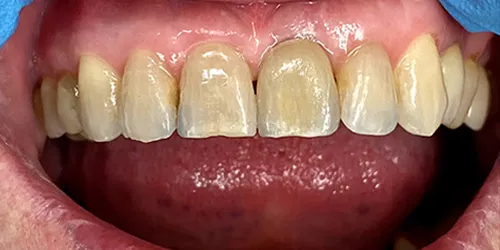

Det er ikke muligt at se forskel på ens egne naturlige tænder og tanden (kronen) på et implantat.

Du vil stort set ikke kunne se eller mærke forskel på dit nye tandimplantat og dine egne, naturlige tænder.